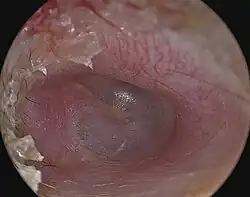

A perforated eardrum (tympanic membrane perforation) is a prick in the eardrum. It can be caused by infection (otitis media), trauma, overpressure (loud noise), inappropriate ear clearing, and changes in middle ear pressure. An otoscope can be used to view the eardrum to diagnose a perforation. Perforations may heal naturally or require surgery.

An otoscope can be used to look at the ear canal. This gives a view of the ear canal and eardrum, so that a perforated eardrum can be seen. Tympanometry may also be used.[6]

A perforated eardrum often heals naturally.[2][7] It may heal in a few weeks or may take up to a few months.[2]

Some perforations require surgical intervention.[3] This may take the form of a paper patch to promote healing (a simple procedure by an ear, nose and throat specialist), or surgery (tympanoplasty).[2] However, in some cases, the perforation can last several years and will be unable to heal naturally. For patients with persistent perforation, surgery is usually undertaken to close the perforation. The objective of the surgery is to provide a platform of sort to support the regrowth and healing of the tympanic membrane in the two weeks post-surgery period. There are two ways of doing the surgery: